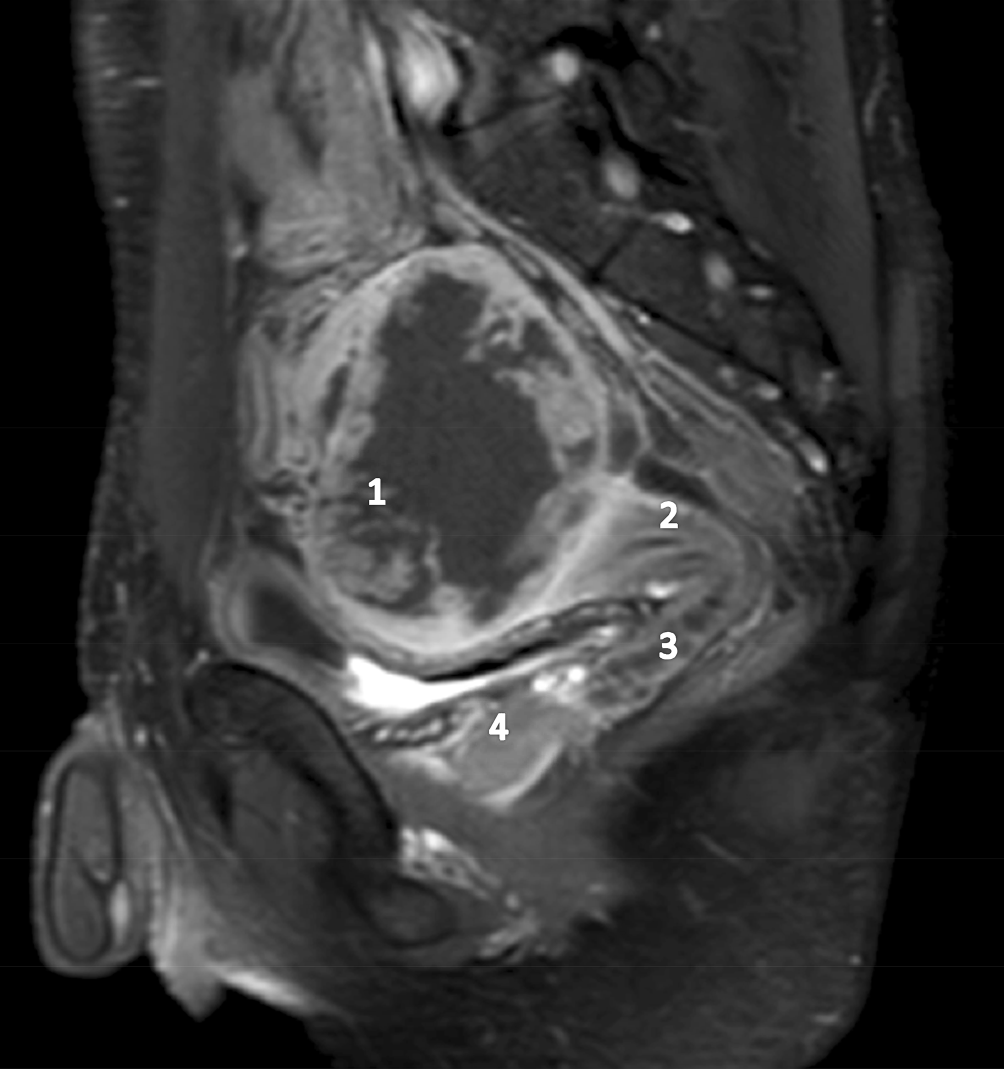

Berichtet wird über einen 24-jährigen Mann mit einem PMDS mit bilateralem Kryptorchismus und Keimzelltumor beidseits. Die Erstvorstellung erfolgte im Februar 2016 mit Schmerzen der linken Flanke. Die körperliche Untersuchung ergab eine zweitgradig hydronephrotische linke Niere, eine palpable Tumormasse im kleinen Becken sowie einen bilateralen Kryptorchismus bei normaler äußerer Virilisierung. Das äußere Genitale war sowohl von der Genitalmorphologie, -funktion und -behaarung unauffällig, eine Hypospadie bestand nicht. In der Familienanamnese berichtete er, dass sein älterer Bruder als Kind eine einseitigen Orchipexie erfahren hatte und als junger Erwachsener ein Seminom hatte. Die Computertomographie und eine Magnetresonanztomographie zeigten einen 8 cm großen linksseitigen Keimzelltumor im kleinen Becken, einen Uterus mit einem Gebärmutterhals sowie einen kurzen an der Prostata anhängenden Vaginalschlauch. Am Uterus waren Tuben, an denen der rechte Hoden bzw. der linksseitige Tumor hafteten. Zusätzlich wurden mehrere vergrößerte paraaortale Lymphknoten mit einem Durchmesser von bis zu 1,6 cm beschrieben. Der rechte, morphologisch unauffällige Hoden befand sich in der Nähe der rechten Iliakalgefäße (Abb. 1). Laborchemisch wurden initial ein βHCG von 5 mlU/ml, AFP 7970 ng/ml (<11 ng/ml) und LDH 393 U/l (<250 U/l) erfasst.

Abb. 1

Magnetresonanztomographie: (1) Linkseitiger Keimzelltumor, (2) Gebärmutter mit Gebärmutterhals und kurzes (3) Vaginalrohr, welches an der (4) Prostata mündet